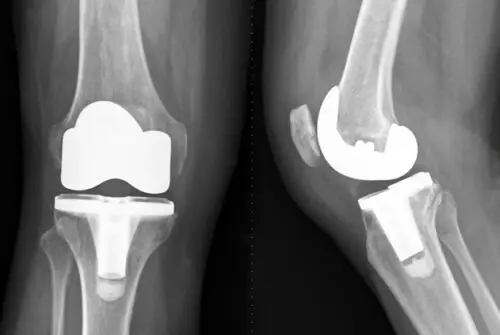

تغيير مفصل الركبة يعتبر من العمليات الشائعة التي تساهم في استبدال المفصل المتضرر أو التالف بآخر صناعي ليساعدك على التحرك بشكل طبيعي والحد من الشعور بالألم، وتكون هذه العملية الحل الأخير للأطباء عند عدم فاعلية الطرق العلاجية الأخرى.

عملية تغيير مفصل الركبة هو إجراء قانوني يقوم به الأطباء حتى يتم استبدال الركبة التالفة بمفصل آخر صناعي، ويلجأ الطبيب لهذه العملية حين يشعر المريض بألم شديد يتسبب في تآكل الغضروف أو تلف الأنسجة الأخرى الموجودة في المفصل.